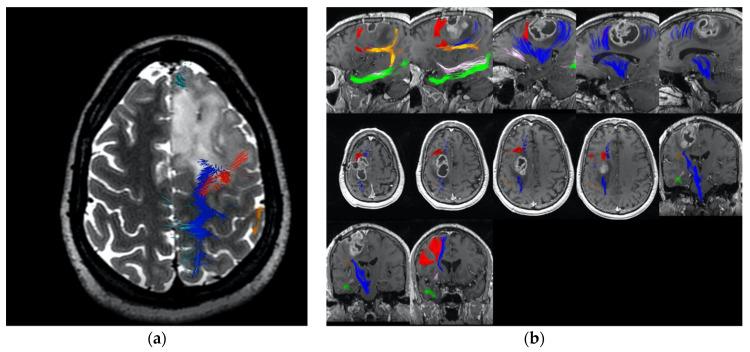

Connectomics is the use of big data to map the brain's neural infrastructure; employing such technology to improve surgical planning may improve neuro-oncological outcomes. Supplementary motor area (SMA) syndrome is a well-known complication of medial frontal lobe surgery. The 'localizationist' view posits that damage to the posteromedial bank of the superior frontal gyrus (SFG) is the basis of SMA syndrome. However, surgical experience within the frontal lobe suggests that this is not entirely true. In a study on = 45 patients undergoing frontal lobe glioma surgery, we sought to determine if a 'connectomic' or network-based approach can decrease the likelihood of SMA syndrome. The control group ( = 23) underwent surgery avoiding the posterior bank of the SFG while the treatment group ( = 22) underwent mapping of the SMA network and Frontal Aslant Tract (FAT) using network analysis and DTI tractography. Patient outcomes were assessed post operatively and in subsequent follow-ups. Fewer patients (8.3%) in the treatment group experienced transient SMA syndrome compared to the control group (47%) ( = 0.003). There was no statistically significant difference found between the occurrence of permanent SMA syndrome between control and treatment groups. We demonstrate how utilizing tractography and a network-based approach decreases the likelihood of transient SMA syndrome during medial frontal glioma surgery. We found that not transecting the FAT and the SMA system improved outcomes which may be important for functional outcomes and patient quality of life.

连接组学是利用大数据来绘制大脑的神经结构;运用此类技术改善手术规划可能会提高神经肿瘤学的治疗效果。辅助运动区(SMA)综合征是额叶内侧手术的一种常见并发症。“定位主义”观点认为,额上回(SFG)后内侧缘受损是SMA综合征的基础。然而,额叶手术的经验表明并非完全如此。在一项针对45例接受额叶胶质瘤手术患者的研究中,我们试图确定“连接组学”或基于网络的方法是否能降低SMA综合征的发生可能性。对照组(23例)手术时避开SFG后缘,而治疗组(22例)使用网络分析和弥散张量成像(DTI)纤维束成像技术对SMA网络和额斜束(FAT)进行测绘。术后及后续随访中对患者的治疗效果进行评估。与对照组(47%)相比,治疗组中经历短暂性SMA综合征的患者较少(8.3%)(P = 0.003)。对照组和治疗组之间永久性SMA综合征的发生率没有统计学上的显著差异。我们证明了在额叶内侧胶质瘤手术中,利用纤维束成像和基于网络的方法可降低短暂性SMA综合征的发生可能性。我们发现不横断FAT和SMA系统可改善治疗效果,这对功能预后和患者生活质量可能很重要。